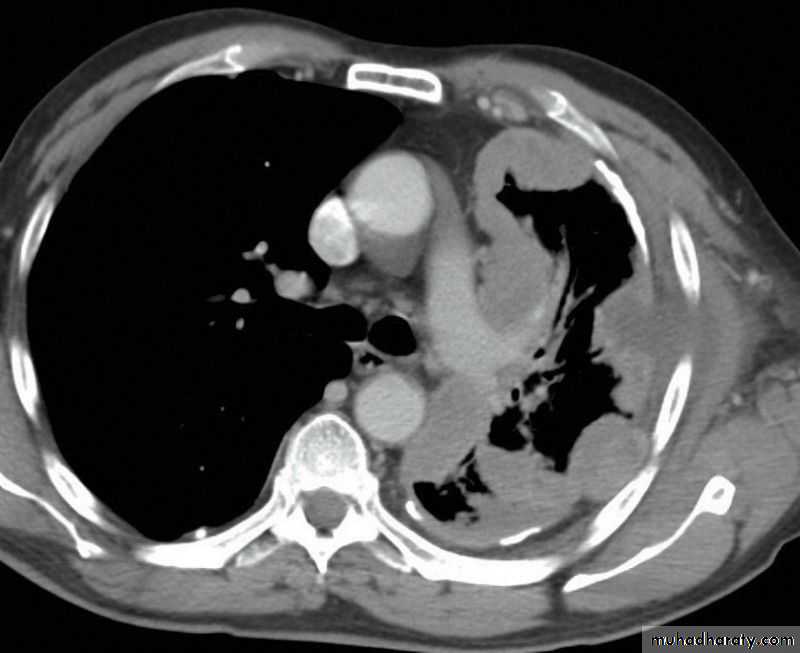

Severe dyspnea with shock